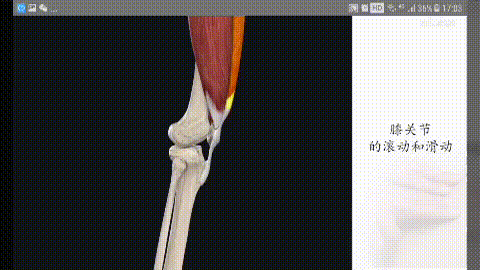

Structure d'extension de l'articulation du genou

Nous nous appuyons sur nos deux jambes pour marcher, nous devons donc étendre les articulations de nos genoux pour nous aider à déplacer notre centre de gravité. Le genou peut être fléchi vers l'arrière, mais il n'y a en principe pas de mobilité vers l'avant et vers les côtés afin de maintenir la stabilité de nos articulations du genou. La base du maintien de cette stabilité repose sur les quatre éléments indispensables de l'articulation du genou :

(i) le muscle quadriceps comme source d'énergie ; (ii) la rotule ; (iii) le tendon rotulien ; et (iv) le point d'action de la tubérosité tibiale.

Lorsque l'on étire le genou, on constate que la rotule se déplace avec la flexion et l'extension de l'articulation du genou, et que le son émis lors de la flexion et de l'extension de l'articulation est en fait lié au mouvement de la rotule. Sous la rotule se trouve ce que l'on appelle le corps adipeux infrapatellaire, qui est un élément important de la structure de l'extension de l'articulation du genou ; le corps adipeux infrapatellaire a un effet amortisseur dans le mouvement et permet de conserver une structure harmonieuse pour le mouvement d'extension de l'articulation du genou.

D'une manière générale, ce type de structure peut entraîner une certaine usure lors de l'utilisation répétée de l'articulation du genou, ce qui a un impact sur son mouvement, et un bruit de cliquetis lors du mouvement peut en être l'une des manifestations.